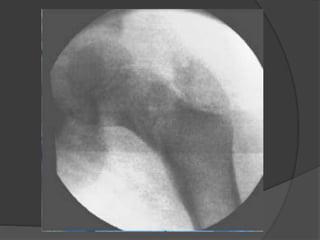

• 8.

Evaluación radiológica  Rxanteroposterior y proyección cruzada de la cadera afecta  TAC y RMN  Gammagrafía, después de las 48hs

Clasificación Delbet - ColonnaTipo I: transepifisiaria A: No luxada B: luxada  Tipo II: transcervical  Tipo III: basecervical  TipoIV: Intertrocanterica

Tipo 1  Menosfrecuente  Incidencia del 8% de las fracturas del cuello  Presentan necrosis avascular en el 70% de los casos  Mejor pronostico en menores de 2-3 años